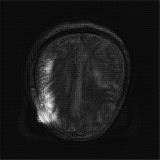

We obtain a subject-wise mean Dice score of 32.94% without any post-processing. By using a simple post-processing with erosion and dilation with filters, this number improves to 48.20% mean Dice score. In comparison, a similar study conducted by [3] consisting of a multitude of algorithms including AnoVAEGAN [4] and f-AnoGANS, obtained a best mean score of 27.8% Dice after post-processing by f-AnoGANS. Before post-processing the best method was Constrained AutoEncoder [8] with a score of 9.7% Dice. An exhaustive list is presented in Table 1. Figure 4 shows sample images of our results.

We obtain a subject-wise mean Dice score of 63.67% for the brain tumor segmentation. Utilizing a simple post-processing scheme of erosion and dilation with filter, we improve our mean Dice score to 68.01%. Figure 4 shows samples generated by our ASC-Net and Table 2 shows our before and after post-processing results. We attempted to apply f-AnoGANs [34] by following their online instructions and failed to generate good reconstructions as shown in Figure 5. The failure of AnoGANs in the reconstruction brings to light the issue with the regeneration based methods and the complexity and stability of GAN-based image reconstruction.

We obtain a slice-wise mean Dice score of 32.24% for this liver lesion segmentation, which improves to 50.23% by using a simple post processing scheme of erosion and dilation with filter. Sampled results are shown in Fig. 4. Compared with [42], which obtains a mean Dice score of 40.78% and a standard deviation of 0.43%, we improve the mean Dice score by almost 10%, but has a much larger standard deviation. Unlike [42], where the network is pre-trained on a artificial tumor dataset, and hence the pipeline customized for tumor segmentation, our method do not need such information beforehand. We notice that our standard deviation for BraTS dataset is similar to [27]. This is because novelty/anomaly detection algorithms without a pre-defined task would suffer from the co-morbidities issues discussed in Section 5.